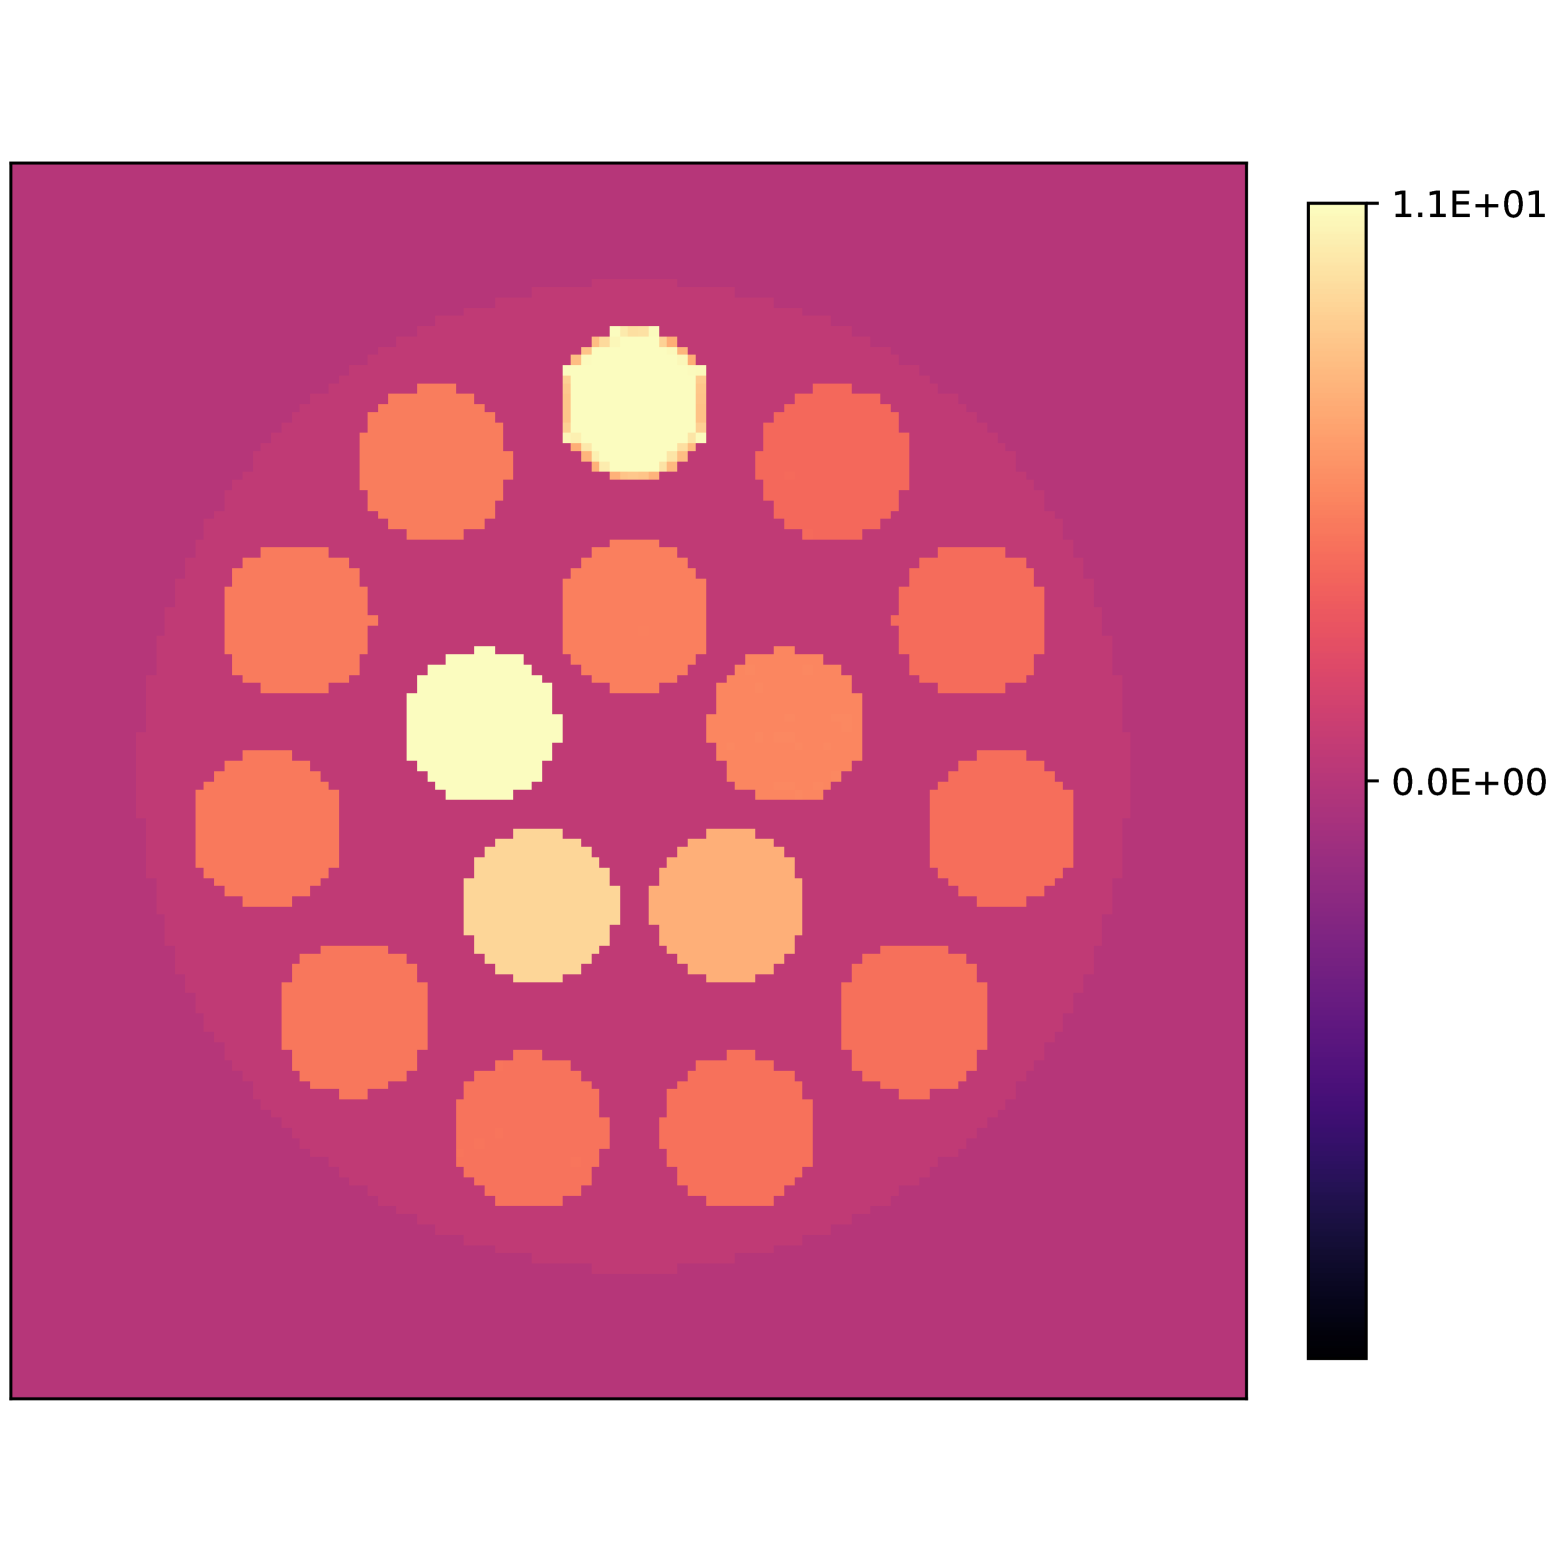

To perform experiments using data from a in vitro water, fat and silicone phantom, we used a publicly available phantom introduced by [29]. It consists of 15 vials with different mixtures of peanut oil and water, and a silicone structure placed the phantom. Following [29] we use a 10-peak peanut oil model for fat, and a single peak at ppm for silicone with a temperature correction of ppm. The phantom was scanned at 3T with a gradient echo multi-echo acquisition with first echo at ms and an echo spacing of ms.

To reconstruct the concentrations and the parameters, we used a bound on the magnitude of the gradient of Hz at voxels with signal magnitude above 10% of the maximum value of the signal accross the entire field of view.

Figs. 3(a), 3(b) and 3(c) show the recovered concentrations of water, fat and silicone, and Figs. 3(e) and 3(f) show the recovered fieldmap and . Fig. 4 shows the error of the recovered Proton Density Fat Fraction (PDFF) compared to the reference values obtained using Magnetic Resonance Spectroscopy (MRS-PDFF). Table 2 details the PDFF measurements in each vial.

Our theoretical results show how the choice of echo times impacts the structure of the solution set. More importantly, this structure is largely independent of the true parameter and the true concentrations and can be computed beforehand to determine which concentrations can be recovered exactly or may experience swap artifacts. Furthermore, our results show that the behavior of the residual around the true parameter can vary significantly. Although the residual has positive curvature near the true parameter, the size of this neighborhood can change substantially depending on the acquisition parameters and the chemical species in the sample. Our results in an in silico phantom also confirm one of our main findings, namely, that the concentrations and can be recovered accurately even if the fieldmap is not accurate. Our results in an in vitro phantom shows that our method achieves an accurate quantification of the MRI-PDFF and a correct separation of the three chemical species in the phantom. In this case, the bound of Hz on the norm of the gradient was critical as otherwise swap artifacts appeared in the recovered silicone concentration, particularly in regions where the fieldmap is large. To analyze the accuracy and precision of the estimations, a comparison with other algorithms is needed. Although this is part of future experiments, our results already show that accounting for significantly reduces the estimation error and achieves a better recovery of the fieldmap.